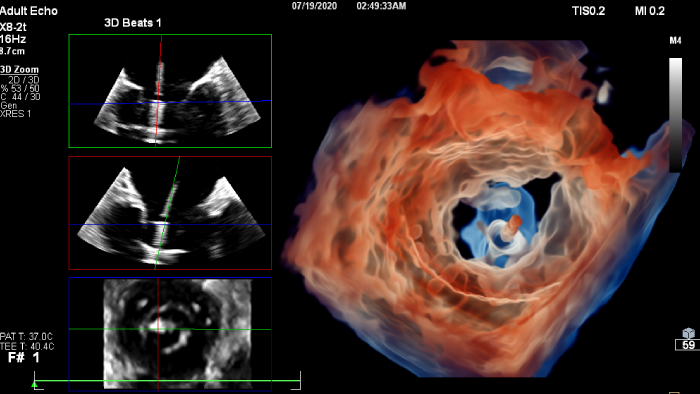

Increase diagnosis confidence and clinical efficiency through superior image quality, advanced quantification tool and automation technology.